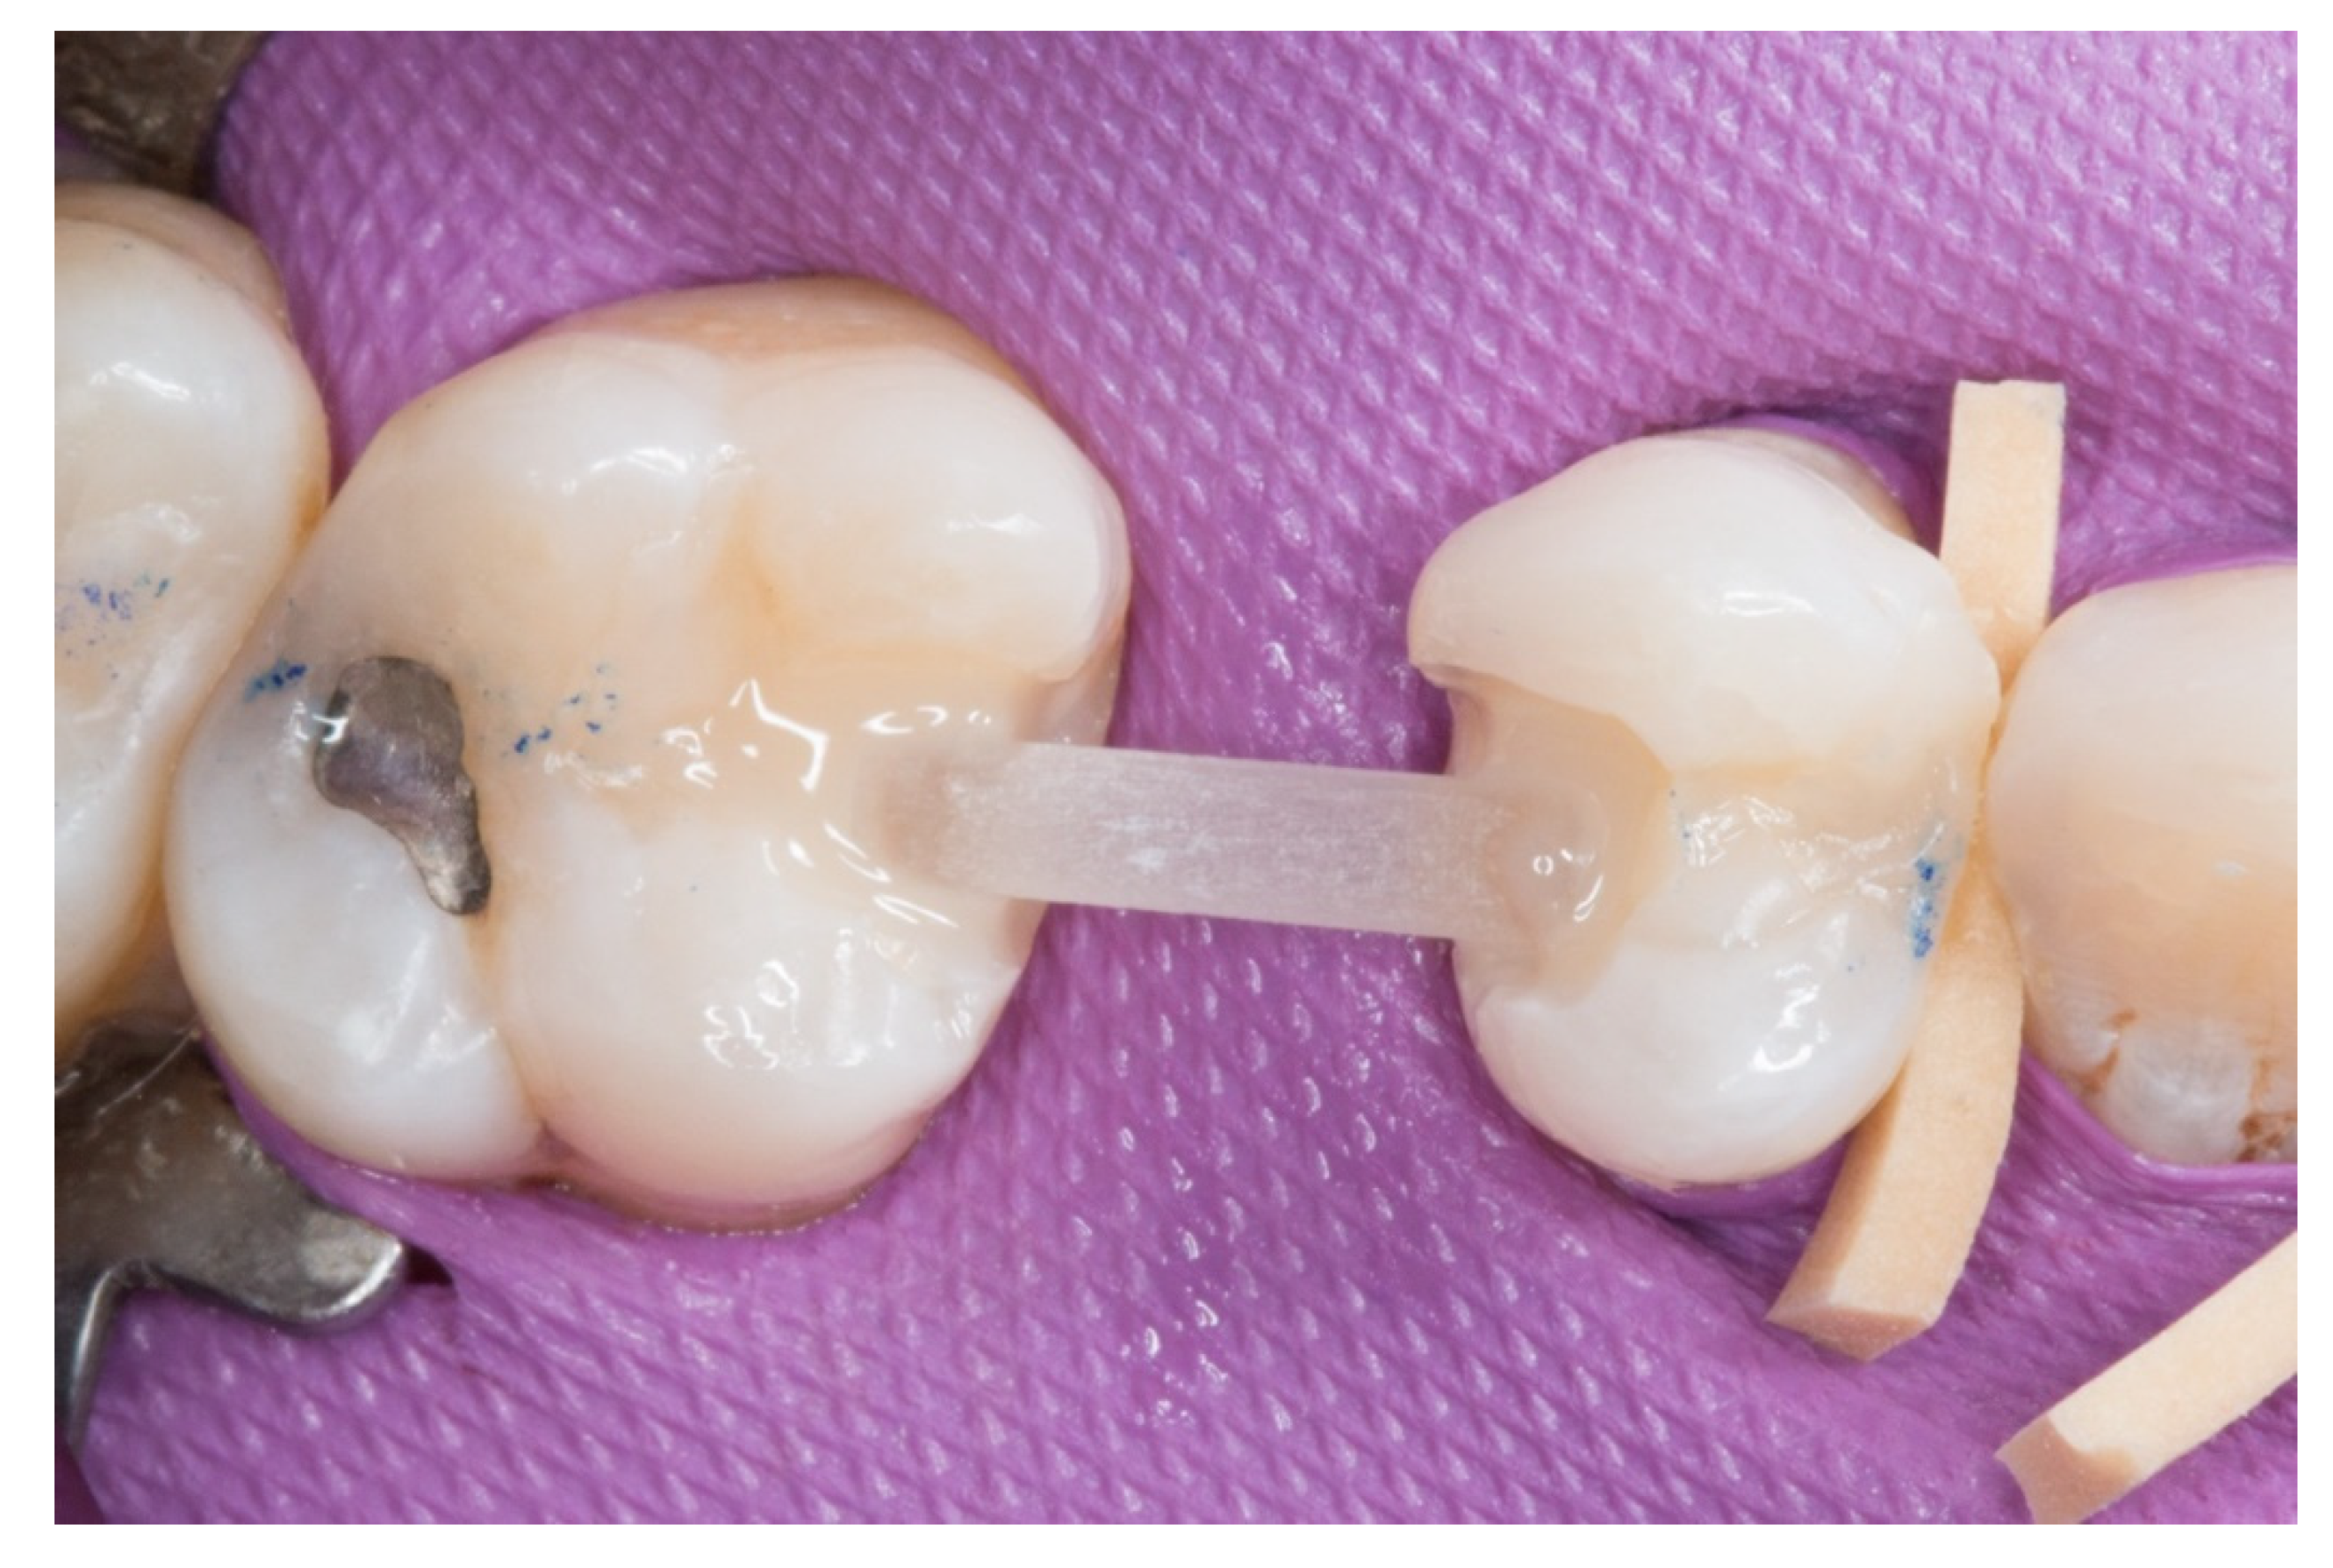

Figure 3.

The transverse structure of the future fiber-reinforced composite bridge (FRCB).

Figure 4.

The horizontal fiberglass pin bonding to the adjacent teeth.

3. The next step consisted of the horizontal fiberglass pin (Rebilda® Post GT, VOCO GmbH, Cuxhaven, Germany) bonding to the adjacent teeth. Firstly, when the isolation of the operative field with the rubber dam was made, the fiberglass pin was adjusted to size and silanization according to the instructions by the manufacturer. Later, the inlay cavities were etched with Ultra-etch® (Ultradent Products Inc, South Jordan, UT, USA) for 20 s, rinsed for 10 s and dried for 10 s. The etched surfaces were covered with a layer of a universal adhesive resin (Prime & Bond® NT, Dentsply Sirona Inc., York, PA, USA), thinned using a brush, and cured for 20 s with a light- polymerizing unit. A flowable resin (Tetric Evo flow®, Ivoclar Vivadent AG, Schaanwald, Liechtenstein) was used to cover the inlay cavities (inlays retainers) and the fiberglass pin to shape the transverse structure of the future bridge (Figure 3 and Figure 4).